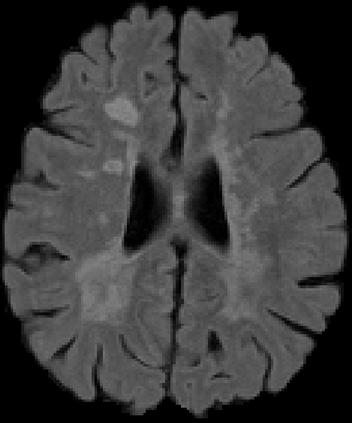

Recently, segmentation methods based on Convolutional Neural Networks (CNNs) showed promising performance in automatic Multiple Sclerosis (MS) lesions segmentation. These techniques have even outperformed human experts in controlled evaluation conditions such as Longitudinal MS Lesion Segmentation Challenge (ISBI Challenge). However state-of-the-art approaches trained to perform well on highly-controlled datasets fail to generalize on clinical data from unseen datasets. Instead of proposing another improvement of the segmentation accuracy, we propose a novel method robust to domain shift and performing well on unseen datasets, called DeepLesionBrain (DLB). This generalization property results from three main contributions. First, DLB is based on a large group of compact 3D CNNs. This spatially distributed strategy ensures a robust prediction despite the risk of generalization failure of some individual networks. Second, DLB includes a new image quality data augmentation to reduce dependency to training data specificity (e.g., acquisition protocol). Finally, to learn a more generalizable representation of MS lesions, we propose a hierarchical specialization learning (HSL). HSL is performed by pre-training a generic network over the whole brain, before using its weights as initialization to locally specialized networks. By this end, DLB learns both generic features extracted at global image level and specific features extracted at local image level. DLB generalization was validated in cross-dataset experiments on MSSEG'16, ISBI challenge, and in-house datasets. During experiments, DLB showed higher segmentation accuracy, better segmentation consistency and greater generalization performance compared to state-of-the-art methods. Therefore, DLB offers a robust framework well-suited for clinical practice.